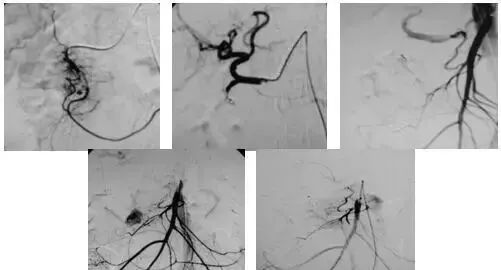

3、肿瘤:

(1)选择性肿瘤供血动脉灌注化疗+栓塞治疗恶性肿瘤。

(2)经皮穿刺注入无水酒精、沸水治疗恶性肿瘤。

(3)应用栓塞术治疗海绵状血管瘤,蔓状血管瘤,子宫肌瘤,骨肉瘤,鼻咽部纤维血管瘤等。